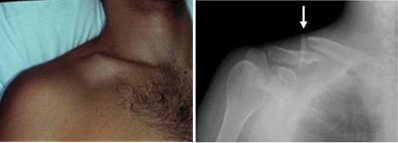

쇄골 골절로 진단된 경우 양 어깨에 8의 모양으로 붕대를 감아 고정하게 됩니다. 대부분의 쇄골 골절은 수술없이도 치료가 가능하다고 알려져 있지만 최근 수술적 치료법의 여러가지 장점이 알려지면서 빠른 회복을 위해 수술적 치료가 선호되고 있습니다. 골절의 형태가 복잡하거나 피부의 손상까지 일으키는 경우, 뼈의 위치의 어긋남이 심한 경우에는 수술이 필요합니다. 수술은 보통 금속판과 나사못을 쇄골에 고정하는 방법을 사용하게 됩니다.